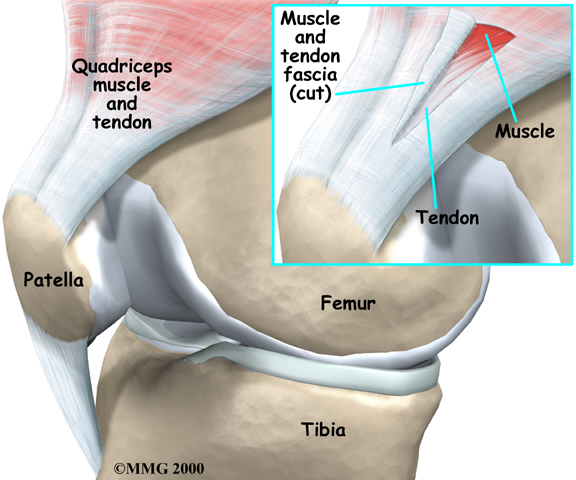

Patellar and Quadriceps Tendonitis

Patellar and quadriceps tendons are located near the knees. Patellar tendonitis refers to inflammation of the tendon that connects the patella (kneecap) to the shinbone. Quadriceps tendonitis occurs when inflammation develops in the quadriceps tendon, which is located directly above the patella where it connects the thigh muscles to the top of the patella. Problems in the knee tendons mostly occur in active individuals who regularly engage in running or jumping. Patellar tendonitis is also called jumper's knee.